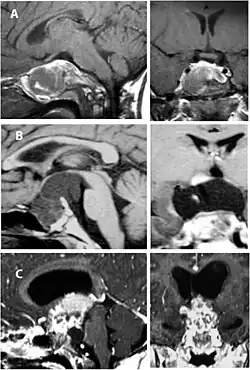

Imaging scans for craniopharyngioma

A physician can conduct a few scans and tests to diagnose a person with craniopharyngioma.[19] High-resolution magnetic resonance imaging (MRI) is commonly used as a diagnostic tool; however, computer tomography (CT) remains the gold standard imaging choice for craniopharyngioma diagnosis as it can detect the severity of the calcification within the tumour.[20]

In some cases, a powerful 3T (Tesla) MRI scanner can help define the location of critical brain structures affected by the tumor. The histologic pattern consists of nesting of squamous epithelium bordered by radially arranged cells. It is frequently accompanied by calcium deposition and may have a microscopic papillary architecture. A computed tomography (CT) scan is also a good diagnostic tool, as it detects calcification in the tumor.[21]

In the adamantinomatous type, calcifications are visible on neuroimaging and are helpful in diagnosis.

The papillary type rarely calcifies. A vast majority of craniopharyngiomas in children are adamantinomatous, whereas both subtypes are common in adults. Mixed-type tumors also occur.[25]

On macroscopic examination, craniopharyngiomas are cystic or partially cystic with solid areas. On light microscopy, the cysts are seen to be lined by stratified squamous epithelium. Keratin pearls may also be seen. The cysts are usually filled with a yellow, viscous fluid rich in cholesterol crystals. Of a long list of possible symptoms, the most common presentations include headaches, growth failure, and bitemporal hemianopsia.

-

CT scan showing a craniopharyngioma -

Enhanced T1 weighted MRIs of craniopharyngiomas -